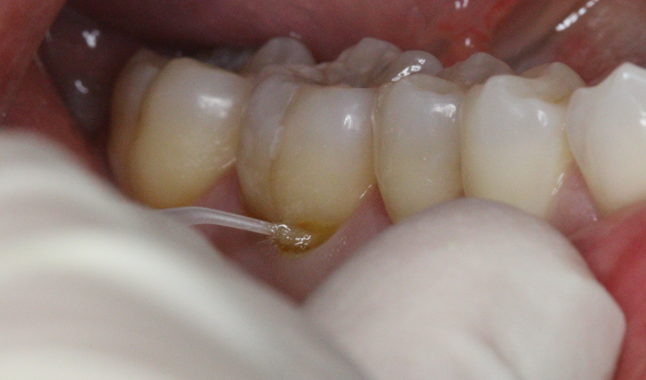

Universal adhesive [Futurabond U; VOCO] placement after total-etch for direct resin [Empress Direct; Ivoclar Vivadent].

On the lower right, there were shallow Class V restorations, which we moved to next. With the entirety of the preparation being in superficial dentin, we had a more highly mineralized dentin and were able to restore using a total-etch approach to maximize the retention of the restoration.